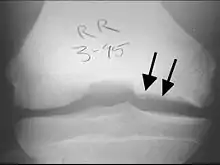

Diagnostic imaging

X-rays show lucency of the ossification on the anterior aspect of the knee in juvenile patients. In older people, the lesion typically appears as an area of osteosclerotic bone with a radiolucent line between the osteochondral defect and the epiphysis. The visibility of the lesion depends on its location and on the amount of knee flexion used. Harding described the lateral X-ray as a method to identify the site of an OCD lesion.[36]